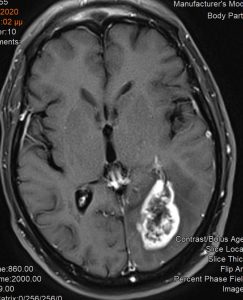

Ασθενής άνδρας, 65 ετών ο οποίος παρουσίασε αρχικά αίσθημα κόπωσης και διαλείπουσες κεφαλαλγίες. Ο νευροαπεικονιστικός έλεγχος με μαγνητική τομογραφία με σκιαγραφικό ανέδειξε χωροκατακτητική εξεργασία στην περιοχή του αριστερού σφηνοειδούς λοβίου με επέκταση και υποεπενδυματική διήθηση του ινιακού κέρατος.

Η μετεγχειρητική μαγνητική τομογραφία εγκεφάλου )βλ. εικόνα) εντός 48ωρου επιβεβαιώνει την ολική εξαίρεση του όγκου.